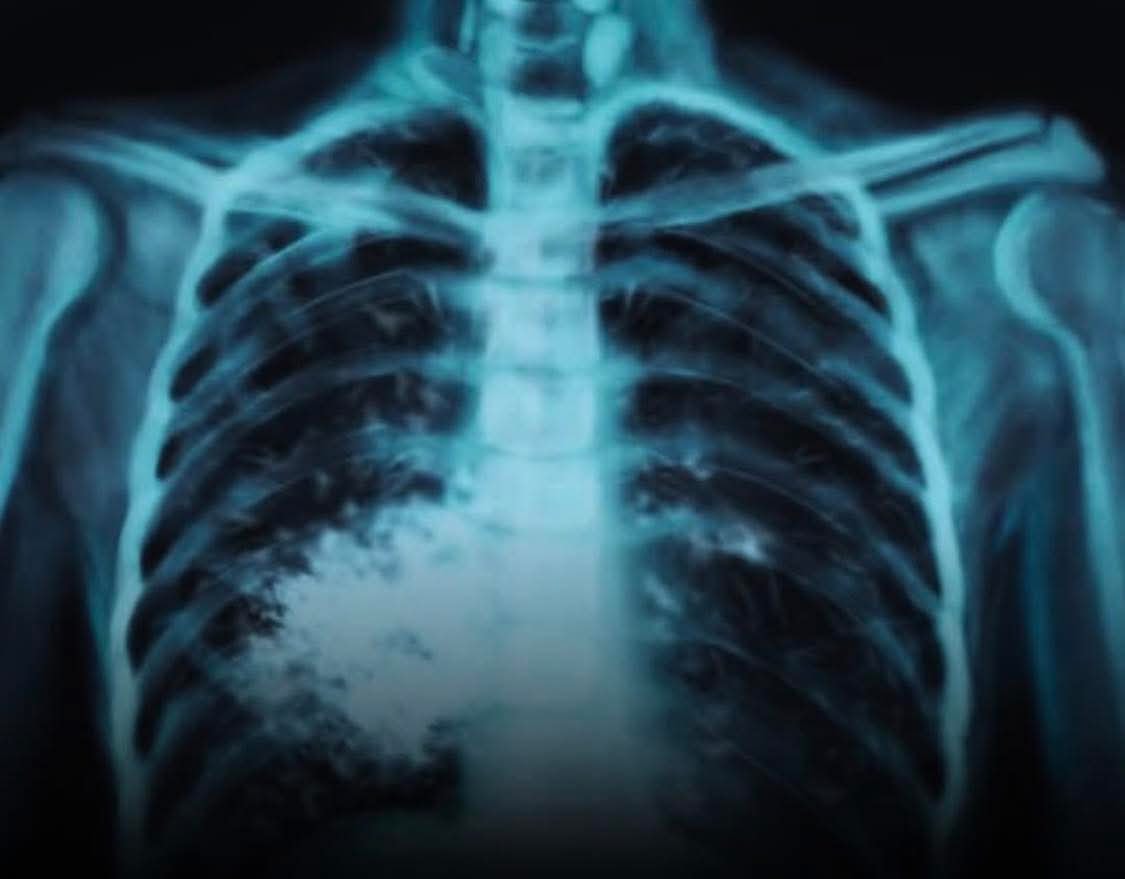

Oui, le vapotage est officiellement associé à des maladies pulmonaires graves et potentiellement irréversibles, comme la Maladie Pulmonaire Associée au Vapotage (MPAV) (EVALI aux USA), caractérisée par une inflammation aiguë, des lésions tissulaires, une toux, un essoufflement et nécessitant parfois une hospitalisation en soins intensifs. Bien que les effets à long terme ne soient pas encore totalement connus, l’inhalation des substances chimiques (comme le THC et l’acétate de vitamine E) peut causer des cicatrices permanentes dans les poumons et un rétrécissement des voies respiratoires, rendant le vapotage moins inoffensif que perçu, surtout pour les jeunes et les non-fumeurs.

Lésions pulmonaires irréversibles : Des composants chimiques peuvent endommager les cellules pulmonaires et provoquer des cicatrices et un rétrécissement des bronches.

Symptômes fréquents : Toux chronique, essoufflement, respiration sifflante, production excessive de mucus.